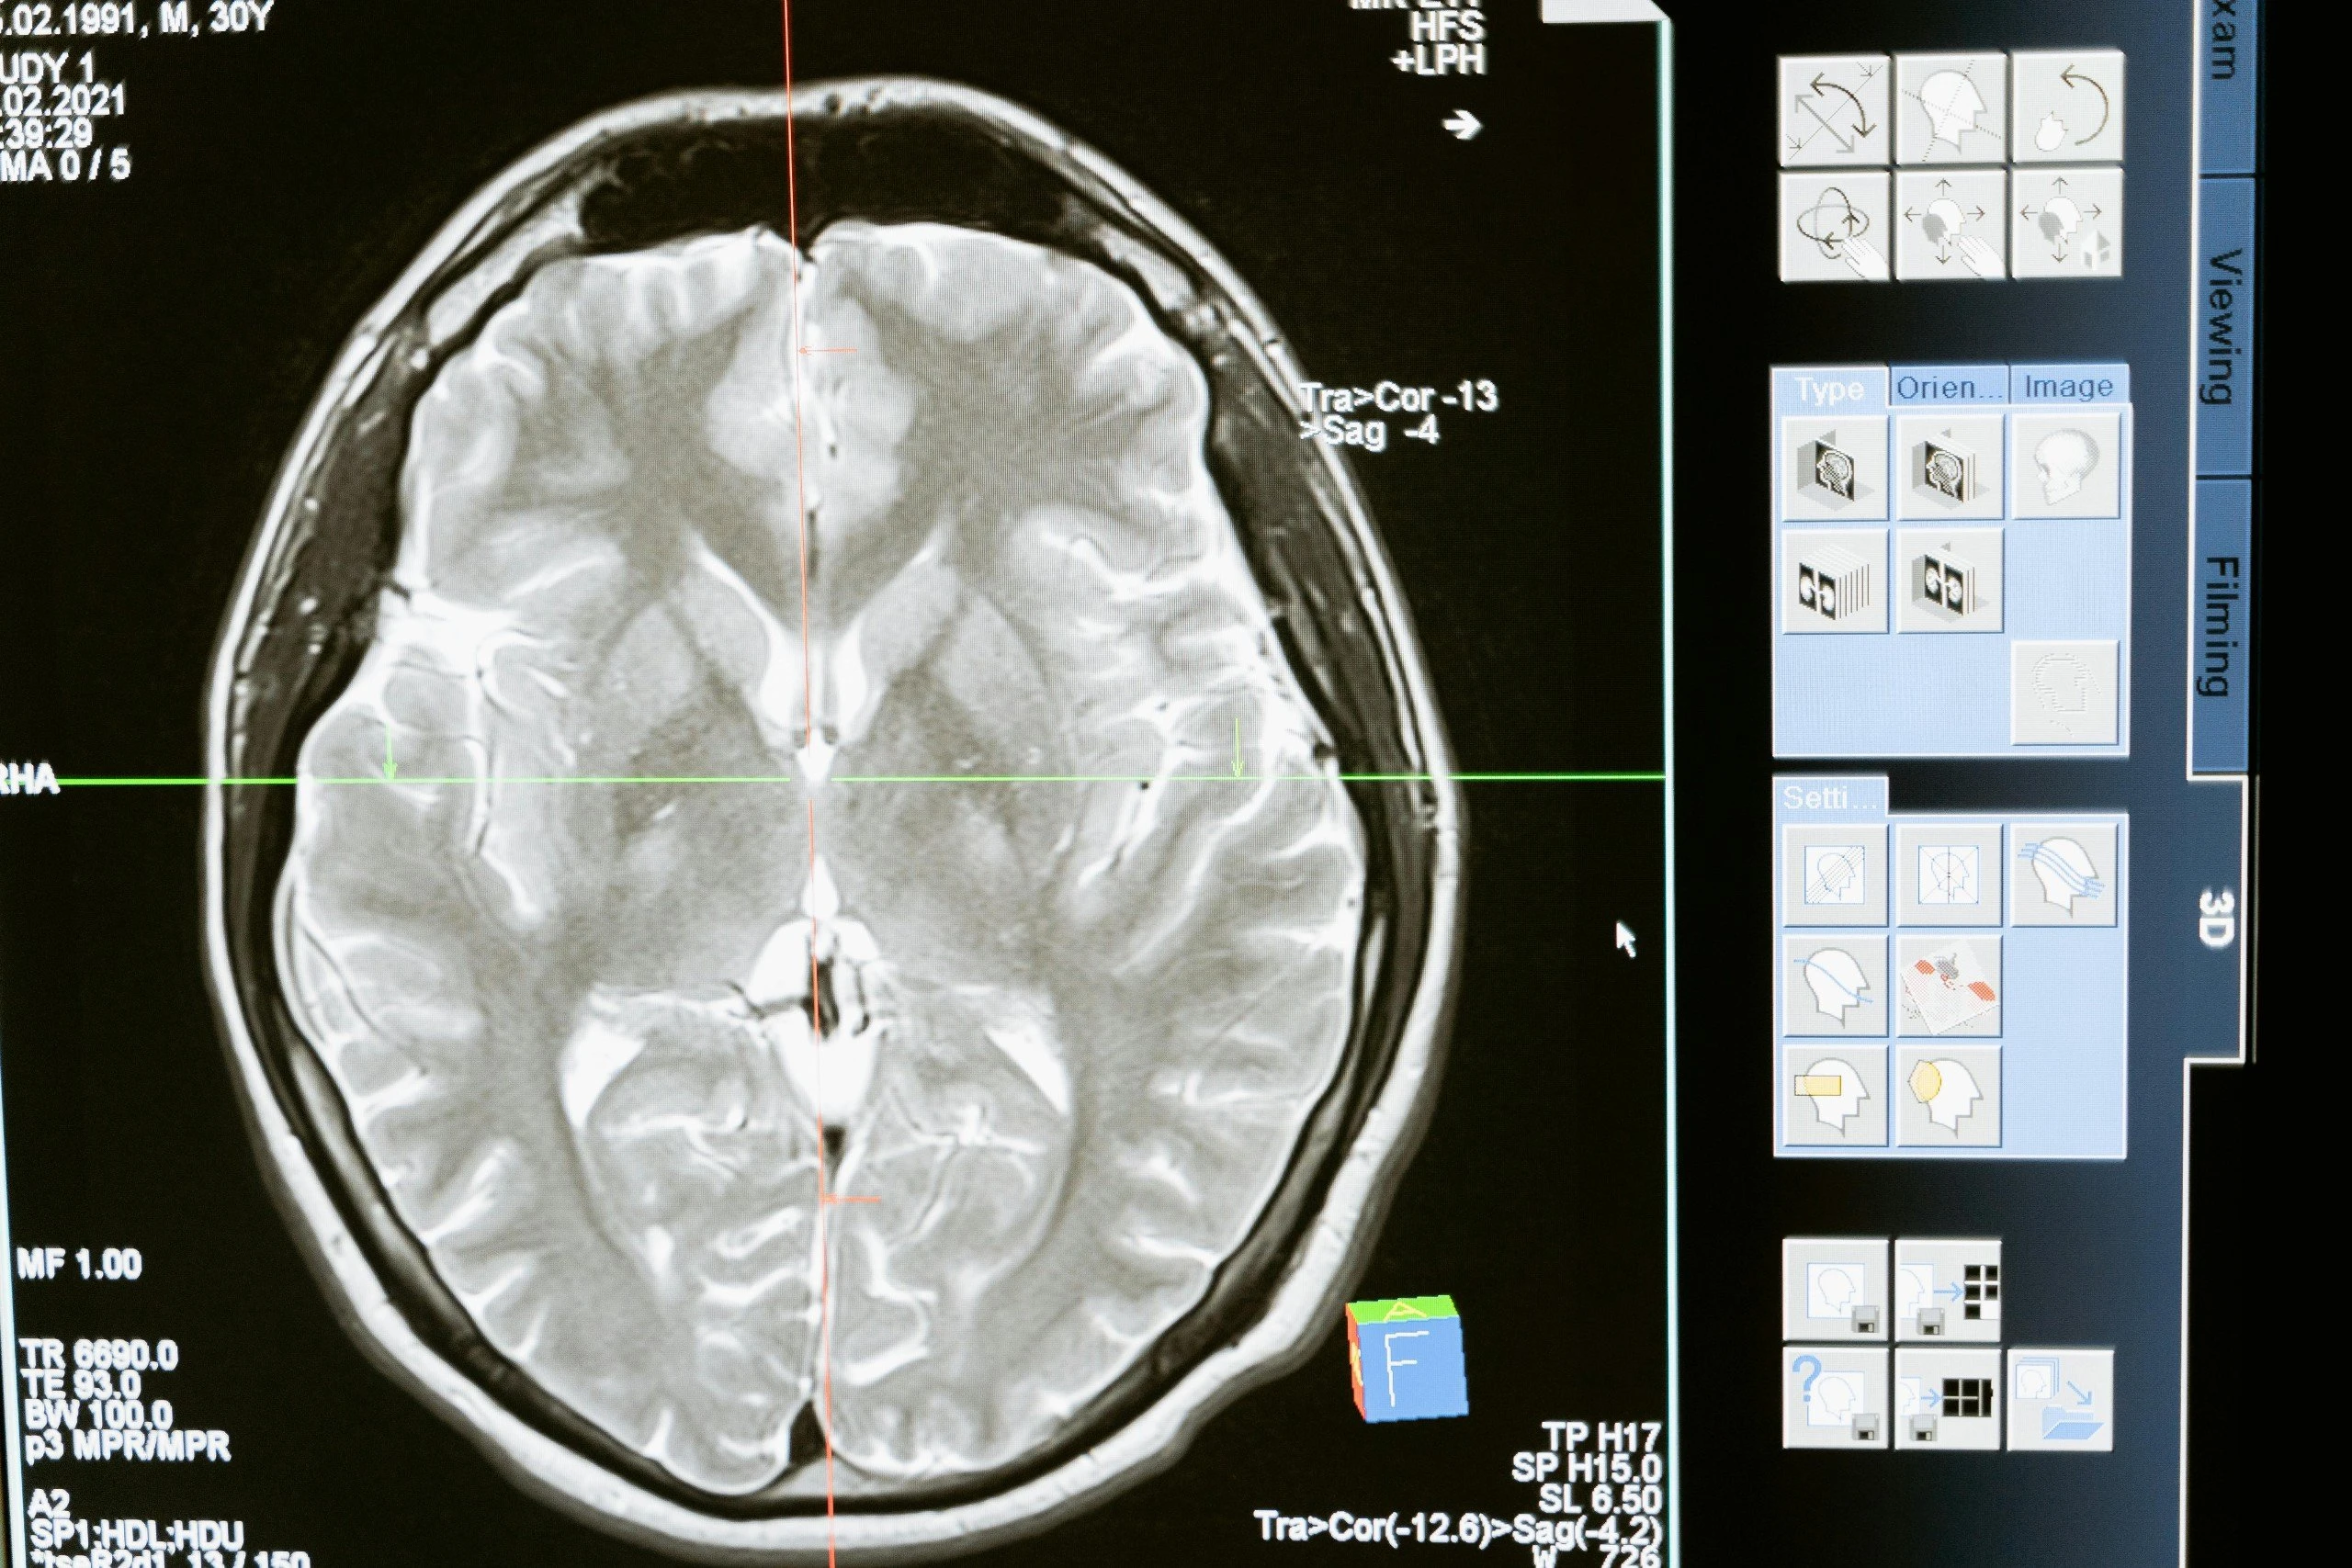

Các nhà nghiên cứu đã "đo" thể tích não bằng phim chụp MRI và dùng trí tuệ nhân tạo (AI).

Khi xem xét kỹ hơn về mô não, họ phát hiện ra rằng những người tập thể dục có khối lượng não lớn hơn ở các khu vực quan trọng - gồm chất xám, giúp xử lý thông tin và vùng hải mã, liên quan đến trí nhớ. Những vùng này có xu hướng teo đi theo tuổi tác, có khả năng làm tăng nguy cơ suy giảm nhận thức và chứng mất trí nhớ, theo Best Life.